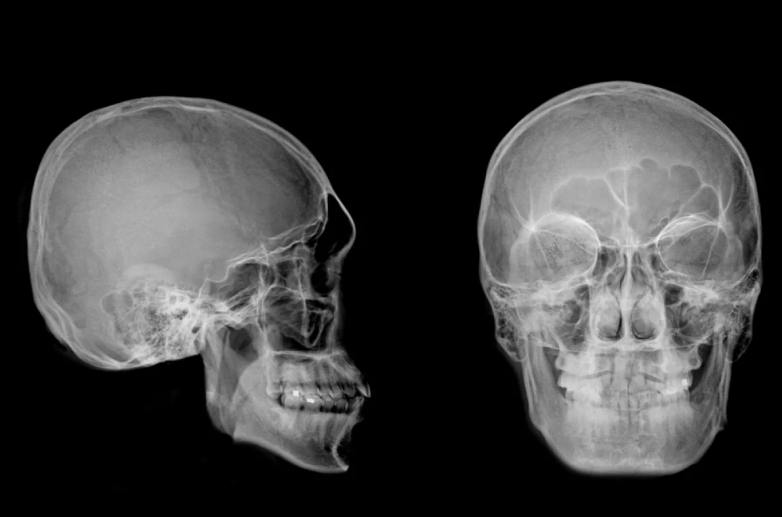

Череп человека – это уникальная, сложная и прочная конструкция, которая защищает наш самый важный орган – головной мозг. Костные пластины, соединённые между собой эластичными швами, образуют не просто «броню», а динамичную систему, которая растёт сама, и обеспечивает нормальный рост и развитие головного мозга. Однако иногда в этой совершенной системе случаются сбои. тогда помочь пациенту может только челюстно-лицевой хирург.

Хирургическое вмешательство начинается с тщательной подготовки. На основе данных компьютерной томографии создаётся точная 3D-модель черепа, что позволяет изготовить индивидуальный имплант и детально проработать план предстоящей операции.